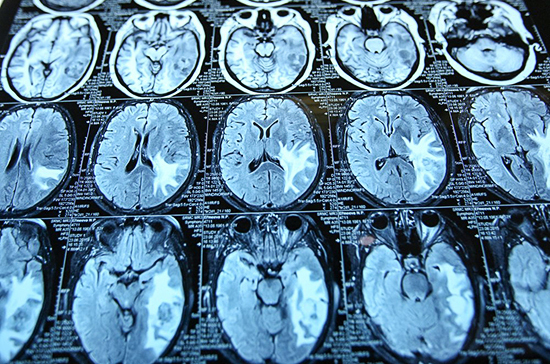

Нейронная активность мозга, связанная с деменцией и эпилепсией, также играет роль в продолжительности жизни человека. К такому выводу пришли ученые из Гарвардской медицинской школы, пишет «Собеседник».

В образцах мозга людей, которые прожили очень долго, показатели белка REST были максимально высокими, а активность мозга, напротив, сниженной. Авторы исследования полагают, что от уровня этого белка зависит в определенной степени не только продолжительность жизни, но ещё и защита от возрастных болезней вроде старческого слабоумия.